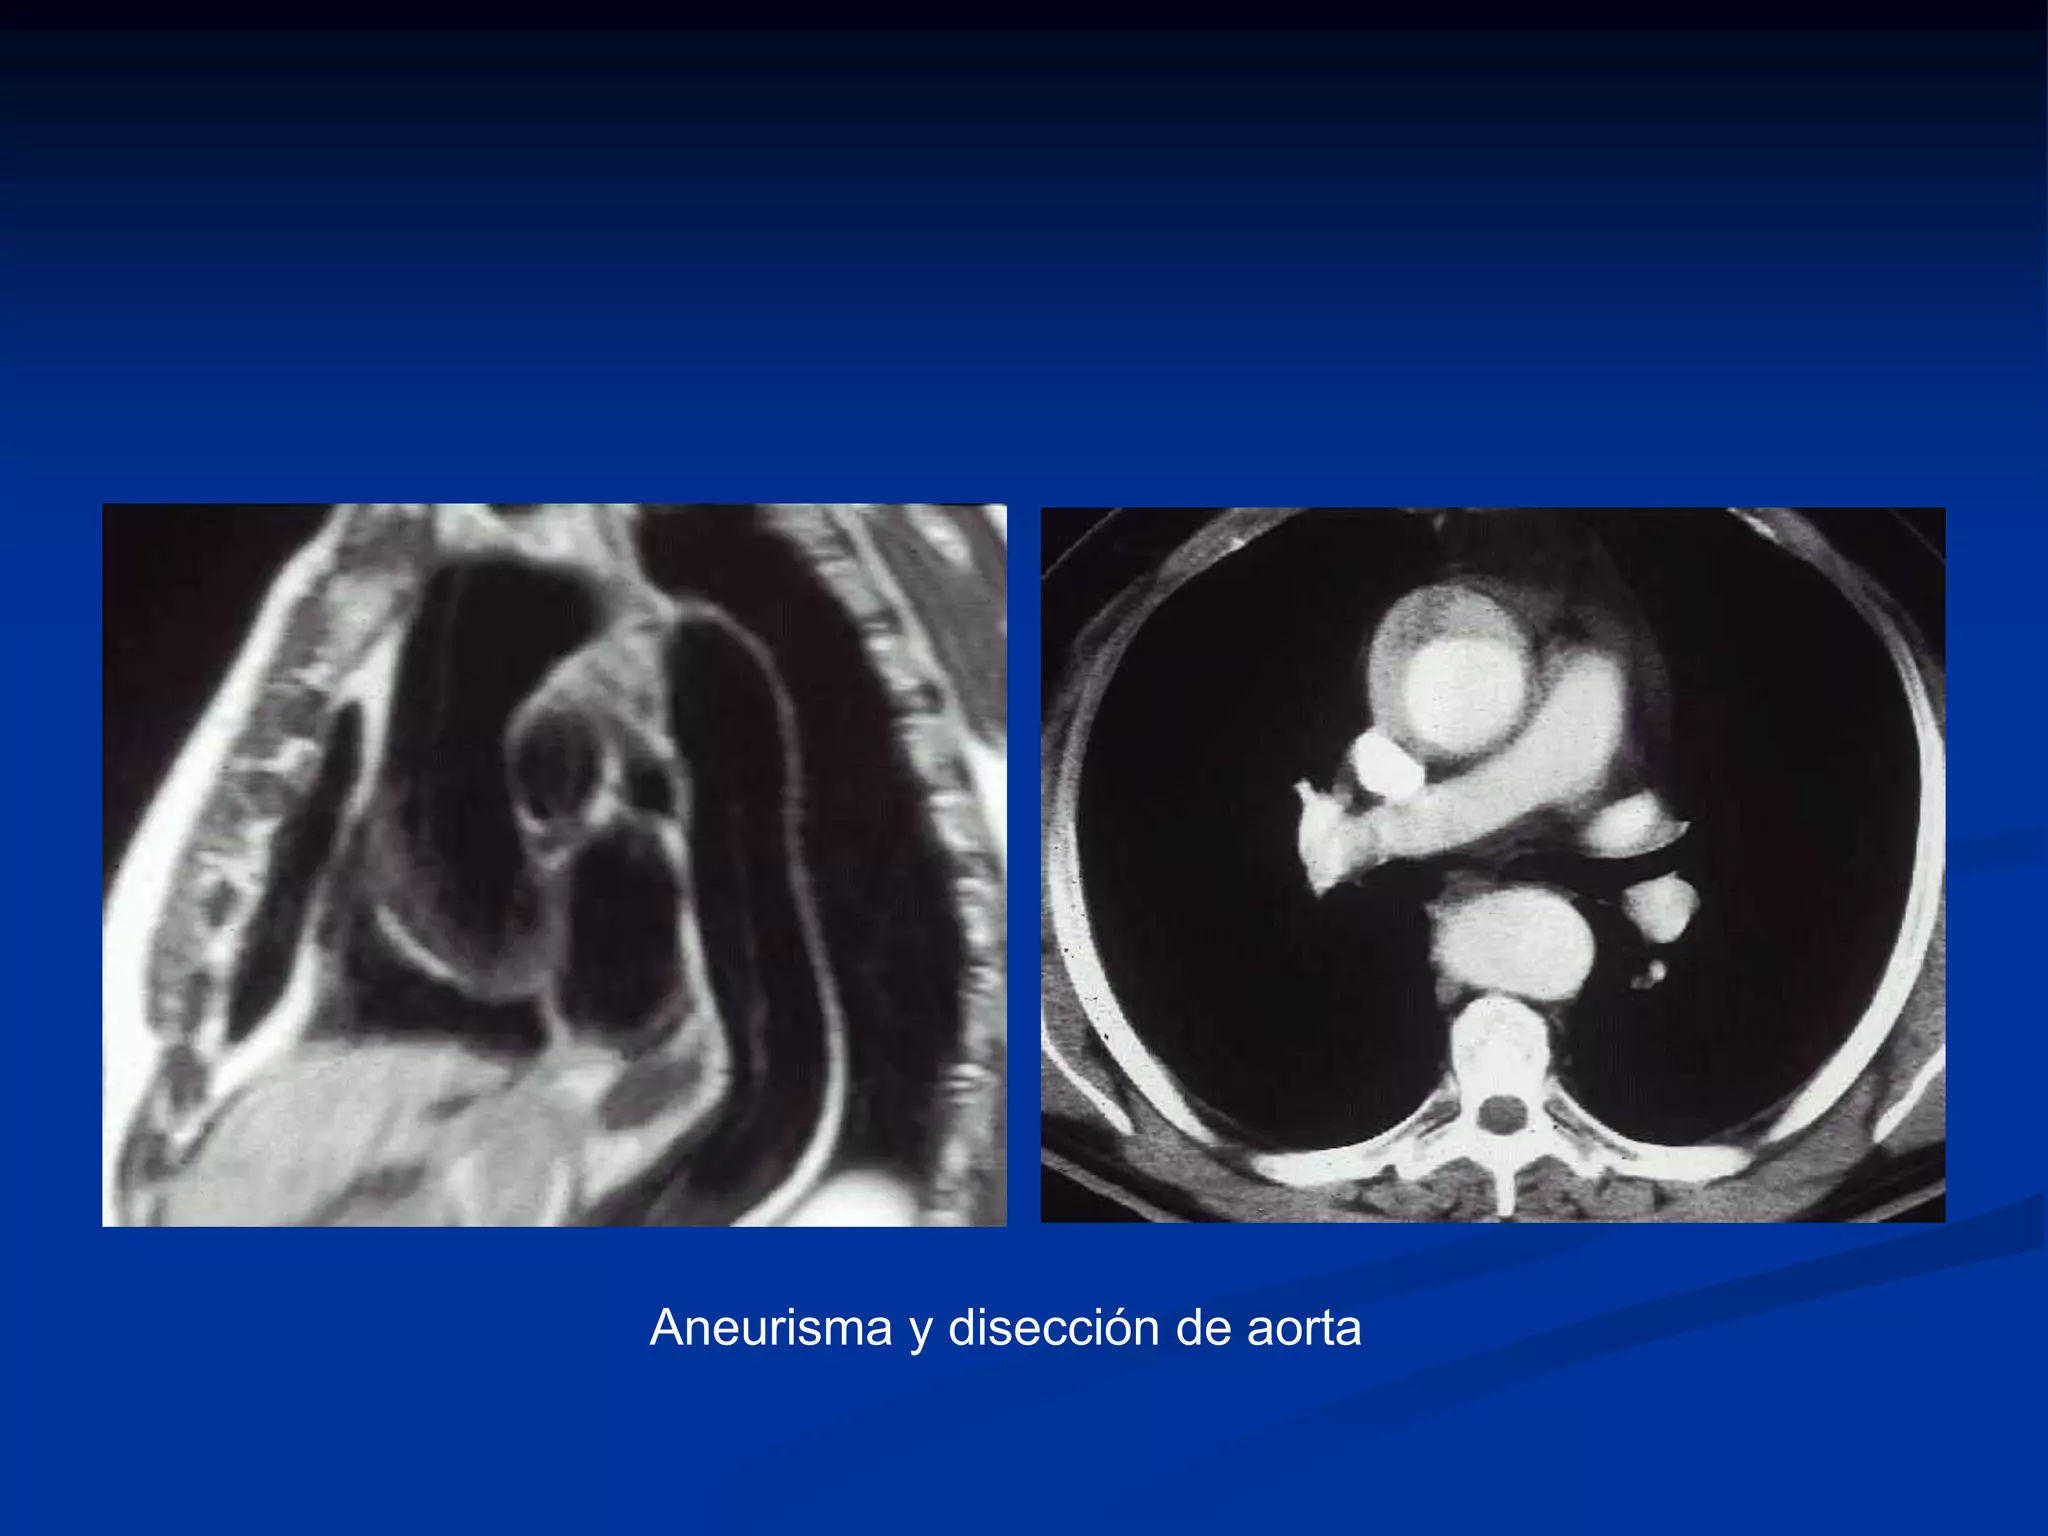

Aneurisma y disección de aorta

Hematoma